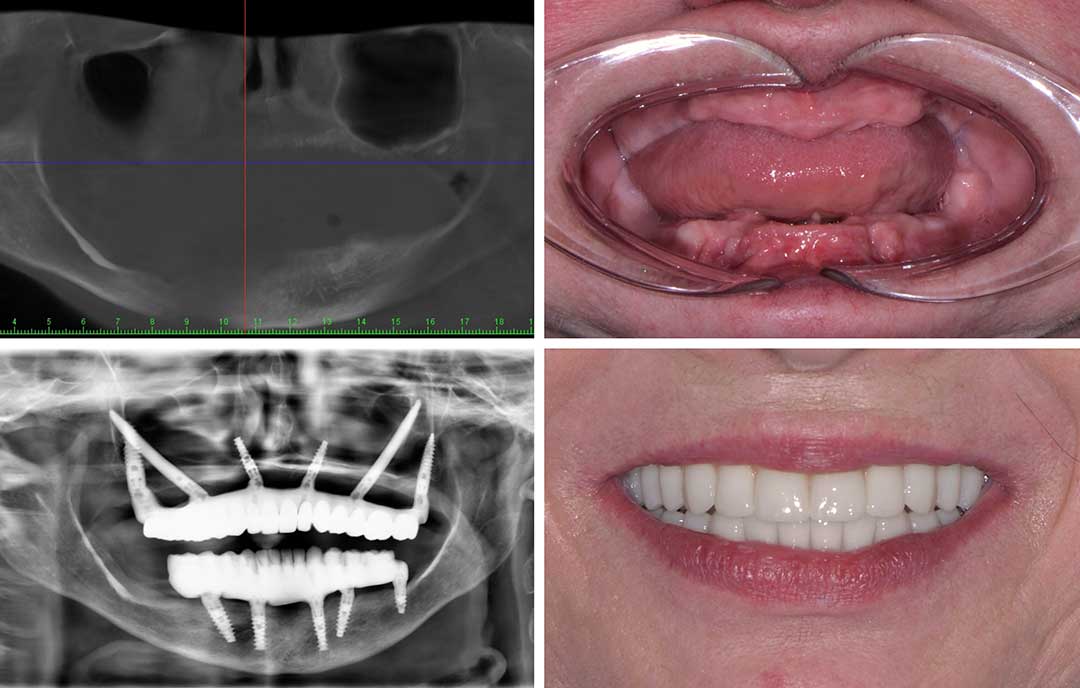

Ausgangssituation

Eine 40-jährige Patientin mit ausgeprägter Zahnarztphobie und desolatem Zahnstatus suchte nach der Möglichkeit einer Behandlung in Vollnarkose. Sie wünschte sich eine allumfassende operative Lösung.Der 42-jährige Patient hatte seine Zahngesundheit infolge ausgeprägter Zahnarztangst über längere Zeit vernachlässigt. Im Oberkiefer waren alle noch vorhandenen Zähne nicht mehr erhaltungswürdig. Aufgrund der fortgeschrittenen Entzündungsprozesse hatte sich der Alveolarknochen vollständig zurückgebildet, sodass nur spezielle Implantatsysteme in Betracht gezogen werden konnten.All-on-4/All-on-6 ermöglicht ohne Augmentationen die Versorgung des vollständigen Zahnbogens auf nur vier Implantaten innerhalb weniger Stunden. Noch am Behandlungstag erhalten Sie einen festsitzenden und sofort belastbaren provisorischen Zahnersatz.

Lösung

In ITN: Navigierte Rekonstruktion des Oberkiefers mit herkömmlichen Implantaten und Pterygoid-Implantaten sowie sofortiger provisorischer Brücke.

Vorteile

Die junge Angstpatientin erhielt die gewünschte Implantatlösung – in kürzester Zeit und unter Vollnarkose.Gerade für Angstpatienten stellt die navigierte Full-Arch-Rekonstruktion eine vielversprechende Option dar: Sie ermöglicht nicht nur eine präzise und schonende Therapie mit festsitzendem Zahnersatz in Vollnarkose, sondern auch eine Rückkehr zu mehr Lebensqualität – oft schon unmittelbar nach dem Eingriff.